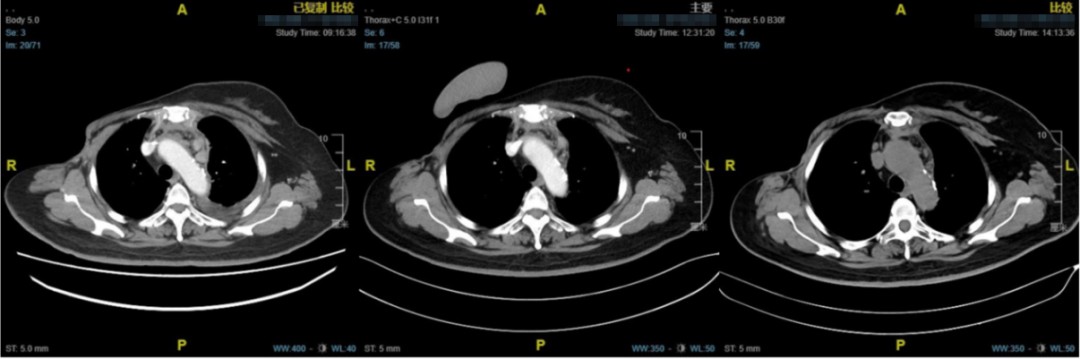

图4.纵隔淋巴结(左:基线;中:2周期后;最近一次复查)

图5.左侧胸腔积液(左:基线;中:2周期后;最近一次复查)